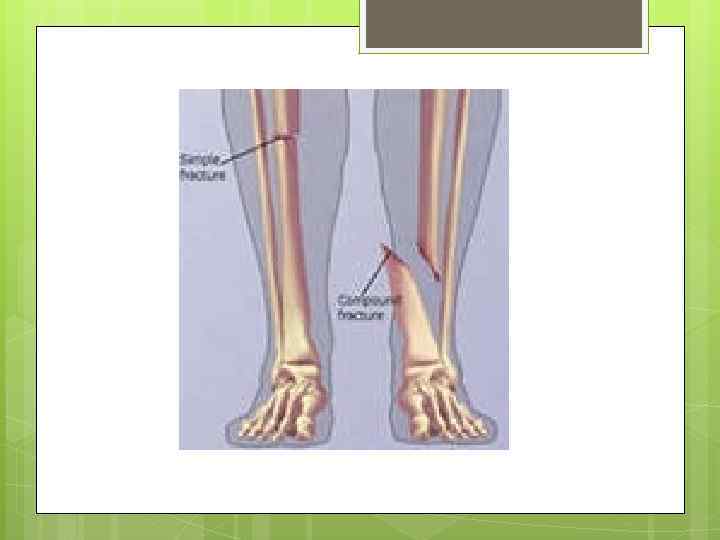

ПЕРЕЛОМЫ Они могут быть закрытыми и открытыми. При закрытых переломах не нарушается целостность кожных покровов, при открытых — в месте перелома имеется рана. Наиболее опасны открытые переломы.

ПЕРЕЛОМЫ Они могут быть закрытыми и открытыми. При закрытых переломах не нарушается целостность кожных покровов, при открытых — в месте перелома имеется рана. Наиболее опасны открытые переломы.

без смещения и со смещением костных отломков. Переломы, при которых образуются только два отломка, называются единичными, переломы с образованием нескольких отломков — множественными.

без смещения и со смещением костных отломков. Переломы, при которых образуются только два отломка, называются единичными, переломы с образованием нескольких отломков — множественными.